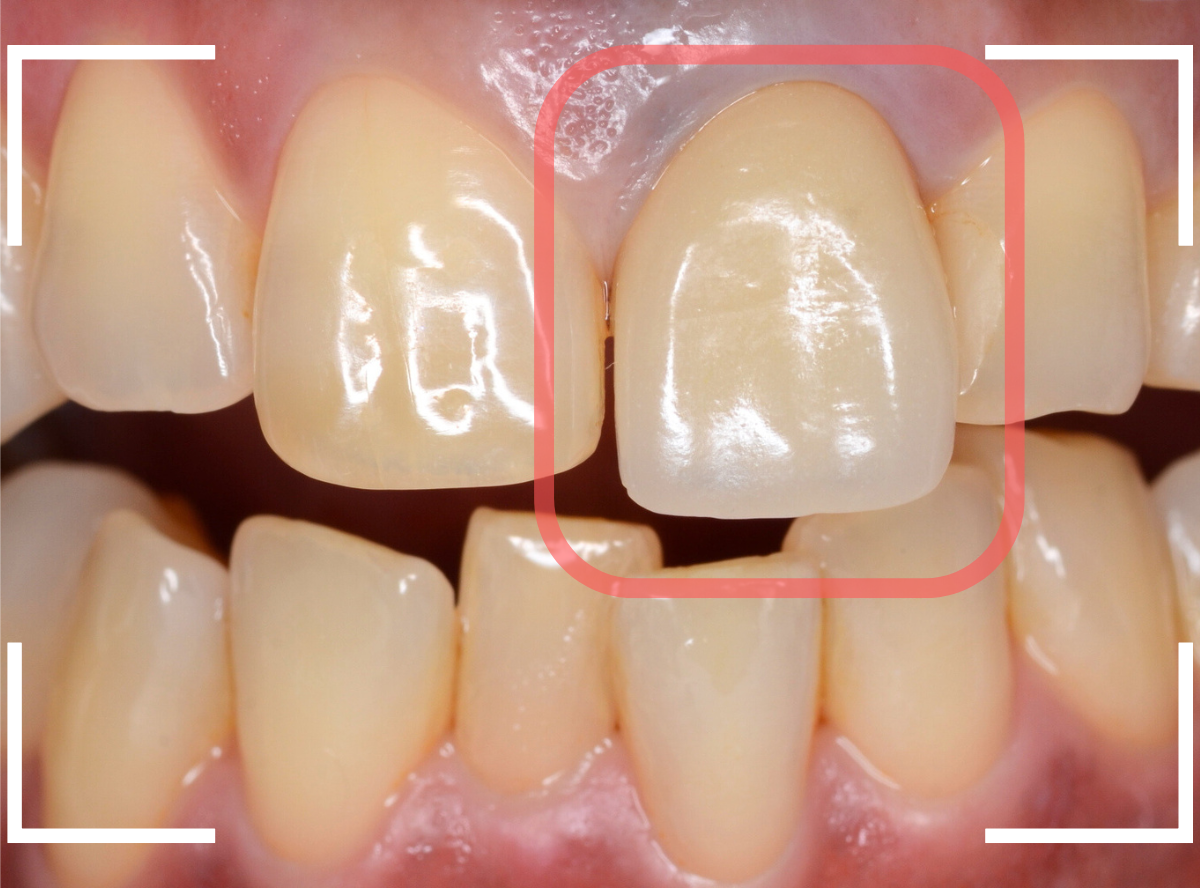

今回は、上の前歯のセラミックの形が気になるので、大分時間も経っているので新規に作り直したいというご希望の患者さんのお話です。

たしかに、隣の歯に比べてかなり下に下がってしまっています。

治療した時の状況がわからないので、治療時からどれくらい下がったのかは正確にはわかりません(><)

裏側を見ると少し歯肉が腫れています。

歯周病の治療と並行して、セラミックの作り直しをすることになりました。

さし歯の中には大きなメタル・コアが入っています。。。

さし歯の周りの歯肉が若干黒ずんでるのも、これが原因でしょう。

せっかくさし歯をやり直すのであれば、このメタル・コアもやりなおしたいところです。

かなり怖かったですが、患者さんにも頑張っていただいて、さし歯を除去後、時間をかけて慎重にメタルコアを除去しました。

無事にメタルコアを除去できましたので、ファイバーコアに置き換えます。

歯肉の治療がひと段落したところで、ジルコニア・セラミックで再製しました。

治療前と治療後の比較、前から見たところです。

患者さんにも満足いただけまして、ホッとしました。

裏側の歯肉も綺麗に治りました。

セラミックの表面はつるつるしていますので、歯周病の原因になるプラークがたまりづらく、治療後の経過も期待できます。